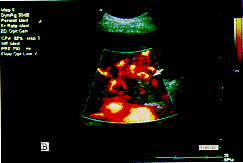

提高肝肿瘤血流信号显示的灵敏性:超声造影后进行能量谐波成像检查能够明显改善能量多普勒超声对肝脏肿瘤周边和内部的血流显示,特别是可显示能量多普勒难以探查到的细小、低速血流,从而大大提高了血流的分辨率。经与能量多普勒超声对照检查,仅被能量谐波成像显示的血流结果见表1。其中1例HCC位于肝尾叶,由于肿瘤位置深,能量多普勒超声检查时未能显示肿瘤内部和周边的血流,声像图也难以确切判定肿瘤是来源于肝尾叶或后腹膜腔;注射超声造影剂后,能量谐波成像检查有效地显示出肿瘤周边和内部血流,以及从肝脏方向来的滋养血流(图1)。

A.能量多普勒超声未显示肿瘤血流信号;

B.注射超声造影剂后,能量二次谐波显示肿瘤周边和内部有丰富的 血流信号

图1 肝尾叶肝细胞癌(箭头所示)